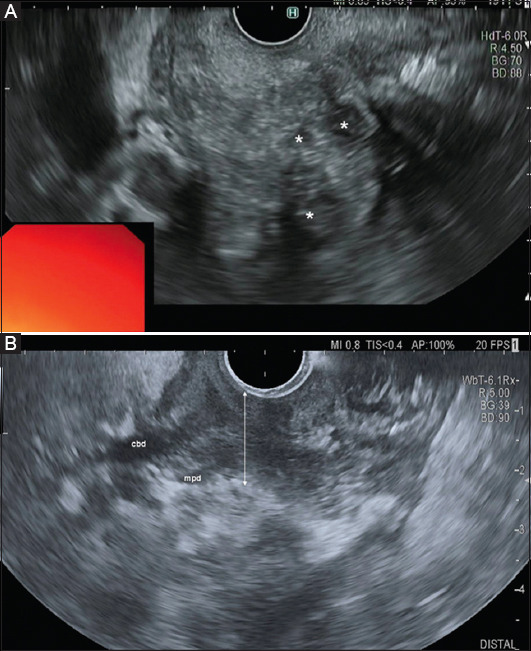

Background: Paraduodenal pancreatitis (PP) is an inflammation involving the groove zone, delimited by the duodenum lumen, bile duct, and the head of the pancreas. This area may also be involved during acute pancreatitis (AP). The differential diagnosis is clinically relevant, since PP generally persists, whereas AP resolves. Hence, we compared a cohort of patients with PP and AP involving the groove area.

Results: The study population consisted of 37 patients (32 men, age 56.9±9.1 years), 25 with a diagnosis of PP (23 men, mean age 54.9±8.5 years), and 12 (9 men, mean age 61.2±9.2 years) with AP involving the groove. All 25 patients with PP and 4 (33.3%) with AP reported a history of alcohol abuse, 23 patients (92%) with PP, and 3 (25%) with AP had a history of smoking. On imaging, PP patients presented a significantly thicker duodenal wall compared to the AP group (P=0.010). Chronic pancreatitis in the body/tail and exocrine insufficiency was prevalent in PP (P<0.001 and P=0.02). The medial displacement of the gastroduodenal artery was more frequent in the PP group (P=0.011).

Conclusion: PP has a different clinical and imaging profile compared to AP involving the groove area.